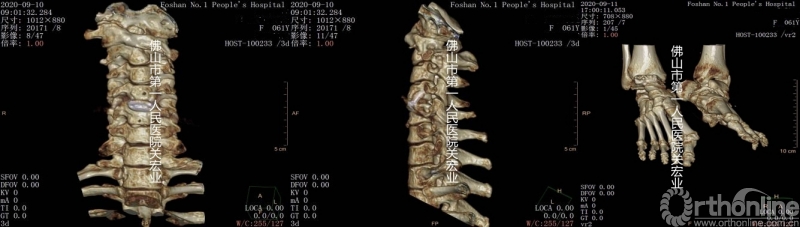

导板与模型

A:和传统置钉相比,这项技术更多的准备工作放在了在术前,术中只允许1-2mm的偏差,所以考验的是医生关于解剖的理解和影像学的分析,术前通过模型就能提前定位置钉位置,术中导板一放,即可置钉,快速且安全。这项技术可以让我们更多的时间用来学习解剖,而不是用在置钉这类机械性的操作上。